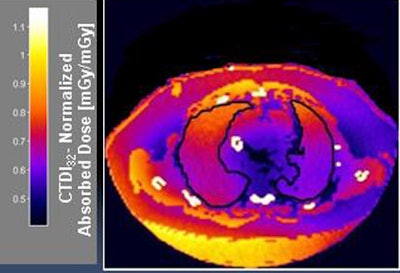

Instead of using the DLP method, the researchers based their dose estimates on individualized dose maps that used the patients themselves as "phantoms" derived from their CT data. The group found that estimates varied by as much as one-third between totals calculated using conventional DLP conversion (k) factors and the new patient dose-mapping technique; in addition, the dose differences between the methods increased with increasing patient size, according to investigators from the Cleveland Clinic, the University of Cleveland, and Philips Healthcare, which supported the study.

"Patient dose derived from patient mapping is more accurate because it takes into consideration the patient size as well as the individual organs," said Carla Thompson in the ECR talk. Thompson is a doctoral student in the applied biomedical engineering program at Cleveland State University and the Cleveland Clinic Foundation.

Each dataset was then "voxelized" to create a patient-specific virtual phantom. Each voxel was assigned a material type based on a priori global HU classification intervals per the International Commission on Radiation Units and Measurements Report 44.

Two readers manually segmented skin, lungs, breast, stomach, liver, and esophagus regions from dose maps, then determined the effective dose.

"Our method is more patient-specific because we're not only including the patient dataset, we also calculate the individual organ dose from each map, and then multiply that by the tissue weighting factor to come up with the effective dose," Thompson said.

The research team concluded that dose estimation differences increased with patient size, and that the dose-map method provided lower estimates of effective dose compared to the DLP method. The lower dose is likely more accurate, especially in these patients, because dose maps account for differences in patient size as well as individual organ size, Thompson said. Patient-specific dose maps could improve CT dose estimation, potentially improving CT dose management, she added.